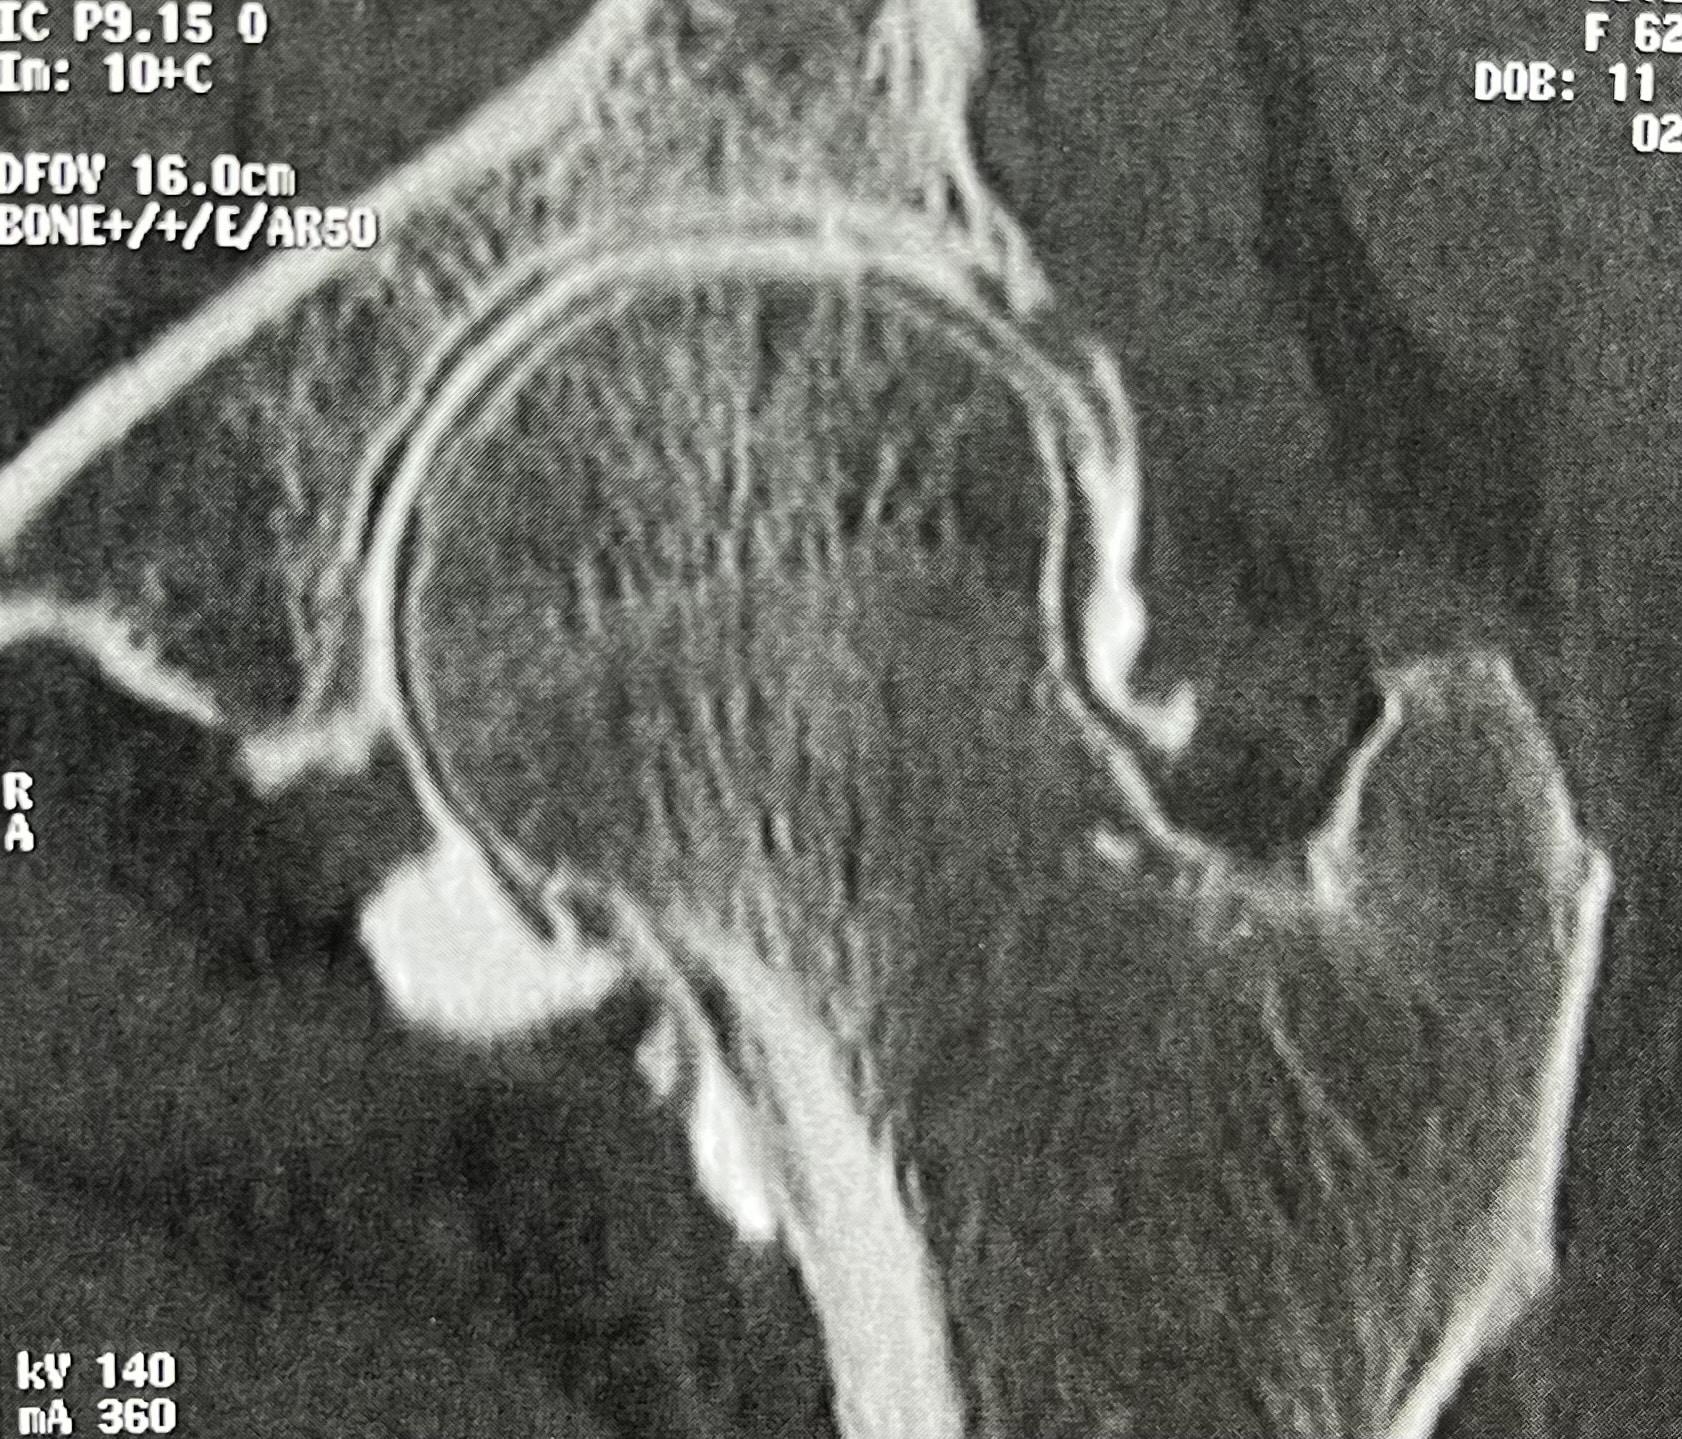

CT arthrography allows precise visualization of cartilage integrity and may demonstrate deep and extensive femoral chondropathy (grade IV), confirming severe joint suffering.

In some cases, the chondropathy is bipolar, affecting both femoral and acetabular cartilage.

Thus, severe and extensive chondropathy may exist despite normal radiographs.